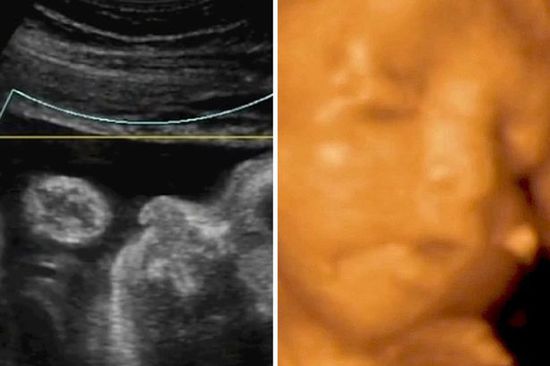

[视频]先进!4D技术实拍腹中胎儿进食打喷嚏 清晰可辨

据英国《镜报》7月27日报道,当先进的4D技术用于扫描胎照时,拍到的画面十分清晰,甚至连胎儿的进食、大哭和打喷嚏的动态都能显示,让人惊叹不已。